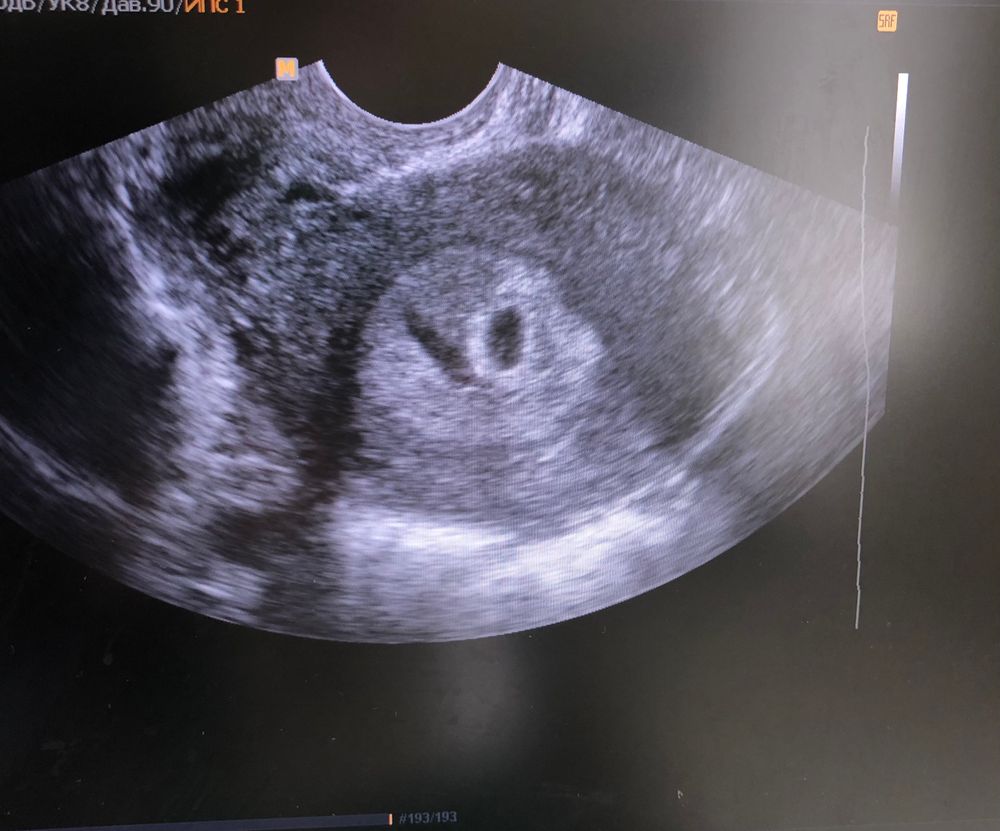

Как по мне похож на эмбрион тот шарик что слева. Вот мое узи на 5-6 неделе Изображение

На вашем снимке качество не очень. Вот вам для сравнения белая точечка это эмбрион, ктр тут 2,4 мм, а прозрачный кружок рядом, это жм Изображение

Аппарат узи какой то... Точнее, качество снимка не ахти. Если придраться, то по мне вооооон там жм, но для эмбриона рановато мне тоже кажется.

Жанна, да сказали ЖМ-2.2мм, но сказали ещё КТР -2.5мм

bravo gun, фото ужасное если честно,снизу на фото прям видно хорошо желточный,он прям ровненькие такой,края горят. Ну по УЗИ ведь в матке? Да! Желточный видно? Да, так чего переживаете то)) увидела или не увидела эмбрион, все будет)) нет поводов паниковать

bravo gun, я, честно говоря, не вижу на вашем снимке эмбрион - только ПЯ Но я и не врач)

Беременность маточная, в матке плодное яйцо. Эмбриона ещё не видно не знаю как они его намеряли , и рано ещё для эмбриона так как поздняя была О

Я тут вижу только плодное яйцо.